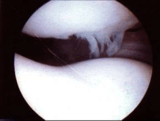

Vue du cartilage normal sous arthroscopie

Pour mieux comprendre, regardez cette coupe d'une articulation : l'os est brun et le cartilage blanc. Les deux cartilages glissent l'un sur l'autre lors des mouvements de l'articulation.

Cette photo est prise lors d'une arthroscopie réalisée pour reconstruire un ligament croisé : un tunnel a été créé dans l'os. On peut voir l'os qui borde le tunnel, et le cartilage normal qui le recouvre.

Ici le cartilage est normal en arthroscopie et sur l'IRM.

Cette image arthroscopique, où l'on peut voir en haut la rotule et en bas le fémur, est l'équivalent de la radio (Défilé fémoro-patellaire, DFP), vue plus haut.

Sous arthroscopie, l'espace entre les deux cartilages est ici dû au liquide (sérum physiologique), dont l'articulation est remplie pour l'opération.

Dans la réalité (hors arthroscopie), la rotule prend appui et glisse sur le fémur, en permanence.

Sur l'image ci-dessus, vous pouvez voir que le cartilage n'est pas lisse en haut, sur la rotule : c'est la chondropathie. Ces petits filaments sont très fins et souples; ils ne gènent pas le glissement des cartilages l'un sur l'autre. De plus, cet image chevelue ne signifie pas que le patient est douloureux, ni que cette chondropathie soit à l'origine des douleurs.